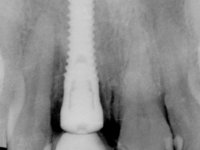

52-year-old female patient, non-smoker. He used an appointment with an implant already placed in the 1.1 site. It was provisionally rehabilitated with a composite resin crown adhered to the palatal surface of the adjacent teeth. This provisional had taken off several times in the last month, even in this first consultation it was taken off. We took advantage of this situation and verified that the “Tissue Level” implant had 2 to 3 mm of prosthetic space available. A deep bite and the inclination of the long axis of the implant posed a very difficult situation for the rehabilitator. If one chooses a abutment with a cemented crown, the height of the abutment would be minimal, with no retention or resistance. If a screwed solution is chosen, the screw access hole would emerge through the vestibular surface. It should be remembered that in 2006 the prosthetic solutions for this situation were limited to these options: 1- Screw-retained angled metal abutment for cemented crown 2 - Screw-retained angled metal abutment for transversally screw-retained crown 3 – Syn Octa metal abutment for screw-retained crown. A serious problem in this rehabilitation was guessed right from the start. The patient had a thick gingival phenotype and good oral hygiene.

After performing an impression of the implant and making the models, we tested several rehabilitative options with the help of the implant brand planning kit. None proved capable. In this sense and as a resource solution, an innovative solution was proposed. It was proposed to make a milled Zr abutment with an appropriate design to receive a veneer that would hide the screw access hole. The veneer itself had a ceramic-coated Zr infrastructure. The goal was to achieve retention and strength by screwing the abutment and aesthetically solve the case with the veneer.

After the impression of the implant using a double-mix technique with double viscosity and the collection of shape and color information by the ceramist, we proceed with the work. In the model, a syn octa was placed over the implant, and a screw was placed on it to assess its emergence in relation to the incisal edge. Then, an adequate emergence profile in the artificial gingiva was prepared. A abutment with characteristics suitable for overbite and simultaneously capable of receiving a veneer was waxed on top of this scenario. This waxing gave rise to the manual milling of a very personalized abutment. An infrastructure in Zr was also made for the veneer with a very great adaptation to the abutment. On this infrastructure ceramics were placed. Ceramic fluorescence sought to compensate for the lack of fluorescence that Zr had and obviously further customize the aesthetics. The adhesive bridge was removed and the definitive work was placed. The syn octa was initially tightened with 35 N to the implant and then the Zr abutment was tightened over the syn octa with 15 N. The access hole was plugged and then the veneer was cemented with resin-reinforced glass ionomer. After 15 years, the patient returned to the consultation with tooth mobility. Fortunately, nowadays we have the possibility of having dynamic tightening wrenches that allow tightening screws with greater inclinations. An access cavity was made without damaging the incisal edge of the veneer. Tightening was done with a dynamic wrench with 15 N torque. The hole was covered with Teflon and filled with composite resin. This solution allowed the problem to be solved in a simple and economical way.